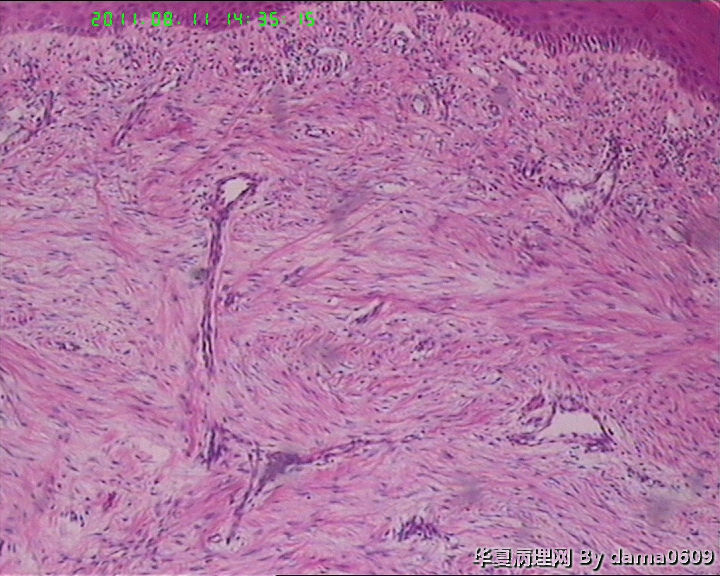

男,14岁,右足第五趾肿物。皮下椭圆形肿物一个,v:2.0x1.7x1.6cm,切面实,灰白,质均,中等硬。

拟诊断:包涵体性纤维瘤病。请老师们指教可否。

(右足第五趾)包涵体性纤维瘤病。

婴幼儿指(趾)纤维瘤病   最特征性的改变是在增生的梭形细胞胞浆内出现包涵体。术后易复发,不转移。